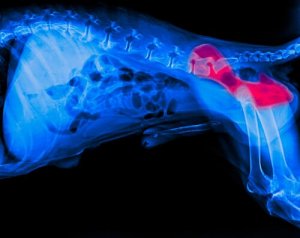

Parliamo di una malattia che colpisce l’anca e le sue articolazioni. Si produce in seguito all’unione difettosa della testa del femore con la sua cavità corrispondente nell’anca. Quando ciò si verifica, i tessuti si degradano e il cane inizia ad avvertire malessere quando cammina, cosa che lo porta a zoppicare.

Vi sono determinati sintomi che possono indicare la displasia dell’anca nel cane. Tra questi, i più frequenti sono un’evidente zoppia, difficoltà ad alzarsi o persino a stare in piedi. Se osserviamo uno di questi sintomi, dobbiamo rivolgerci al veterinario, che sicuramente realizzerà una radiografia per confermare la patologia.